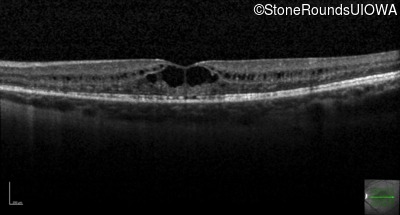

Optical Coherence Tomography - Right - 20/50 +2

Exemplar / OCT Stack